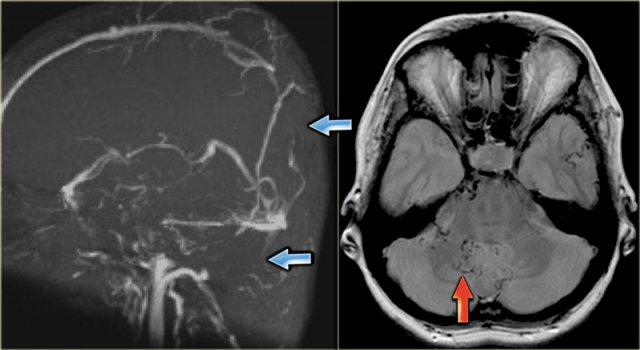

Xoang ngang kém phát triển (hypoplastic)

Kém phát triển (hypoplasia) và bất sản (aplasia) xoang ngang phải hoặc trái là một phát hiện thường gặp.

Tình trạng này có thể dễ dàng bị nhầm lẫn với huyết khối xoang, do trên MRA một trong hai xoang ngang không được hiển thị.

Khi nghi ngờ có xoang ngang kém phát triển, cần quan sát kích thước của lỗ tĩnh mạch cảnh (jugular foramen).

Các hình ảnh bên trái là của một bệnh nhân có xoang ngang trái kém phát triển.

Lưu ý sự chênh lệch kích thước của lỗ tĩnh mạch cảnh hai bên.

Bên trái là ảnh MIP mặt phẳng ngang (transverse MIP) của chuỗi xung tương phản pha (phase-contrast).

Để phân biệt xoang ngang kém phát triển với xoang ngang có huyết khối, cần xem xét các ảnh gốc (source images).

Trên ảnh gốc bên phải, có thể thấy không có tình trạng kém phát triển (mũi tên xanh).

Trong trường hợp này, đây là huyết khối xoang ngang trái.

Bên trái là một trường hợp khác minh họa rằng không thể hoàn toàn dựa vào kỹ thuật tương phản pha (phase contrast imaging).

Tín hiệu trong tĩnh mạch phụ thuộc vào vận tốc dòng máu chảy và thông số mã hóa vận tốc (velocity encoding) do kỹ thuật viên cài đặt.

Ở ngoài cùng bên trái là hình ảnh bệnh nhân không thấy xoang ngang trái.

Điều này có thể do kém phát triển, huyết khối tĩnh mạch hoặc dòng chảy chậm.

Trên chuỗi xung T1W sau tiêm thuốc tương phản từ, có thể thấy rõ ràng xoang ngấm thuốc và còn thông (patent).